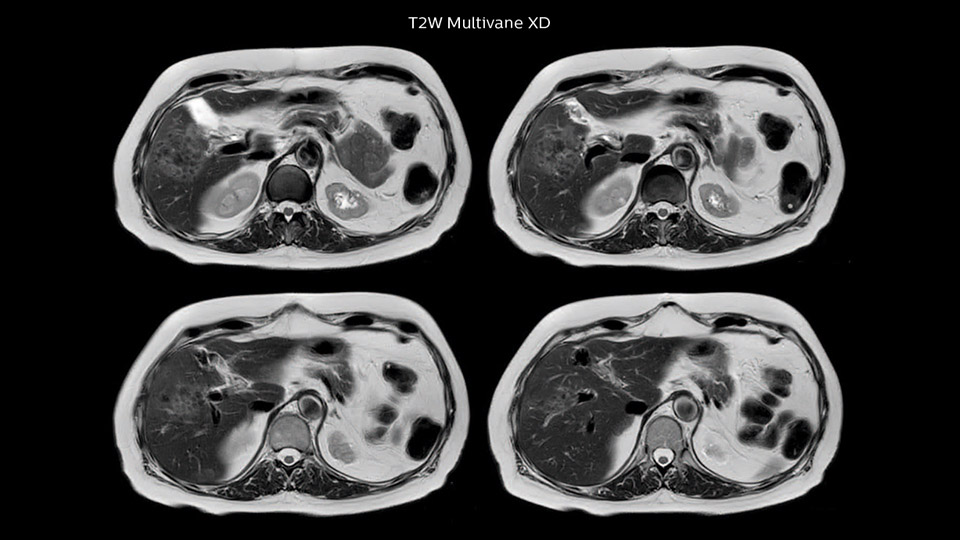

Dr. Baumann then implemented MultiVane XD for motion correction. It uses an extended reconstruction algorithm for imaging that is virtually motion free. “With MultiVane XD we get excellent motion-corrected images with high spatial resolution. We typically first optimize our scan for high image quality, and when satisfied with that, we try to reduce the scan time. So, we combined MultiVane XD with dS SENSE, which allows us to shorten the scan time,” he explains. “The performance of MultiVane XD in liver imaging is outstanding. MultiVane XD with dS SENSE is a powerful development in improving liver image quality.” “As we use breathhold imaging for T2-weighted liver scans, we depend on the patient’s ability to cooperate with the exam. This can present a real challenge when we are looking for small lesions, such as in our oncological patients. However, with MultiVane XD motion correction, we get excellent images. This is important for our surgeons, because they want to know exactly where the lesions are.”

“Our liver exams are quite fast,” says Dr. Baumann. “If the patient tolerates it, we use an arms-up position to reduce the FOV and speed up the exam with dS SENSE.” “We acquire one transversal high resolution T2-weighted sequence with 3 mm slice thickness, for example for pancreas or liver lesions. Then we also add a T2 fat suppressed MultiVane XD SPIR sequence. We perform these two routinely in our liver imaging. We use high dS SENSE factors to significantly shorten scan times to 2-4 minutes, which can improve our protocol; it’s a very robust scan.” “We include mDIXON for the dynamic sequences because of the robust and homogeneous fat suppression we get with that. We had been using eTHRIVE, but we are now quite happy with mDIXON. Sometimes we use a medication to calm the bowels, to further improve the image quality.”